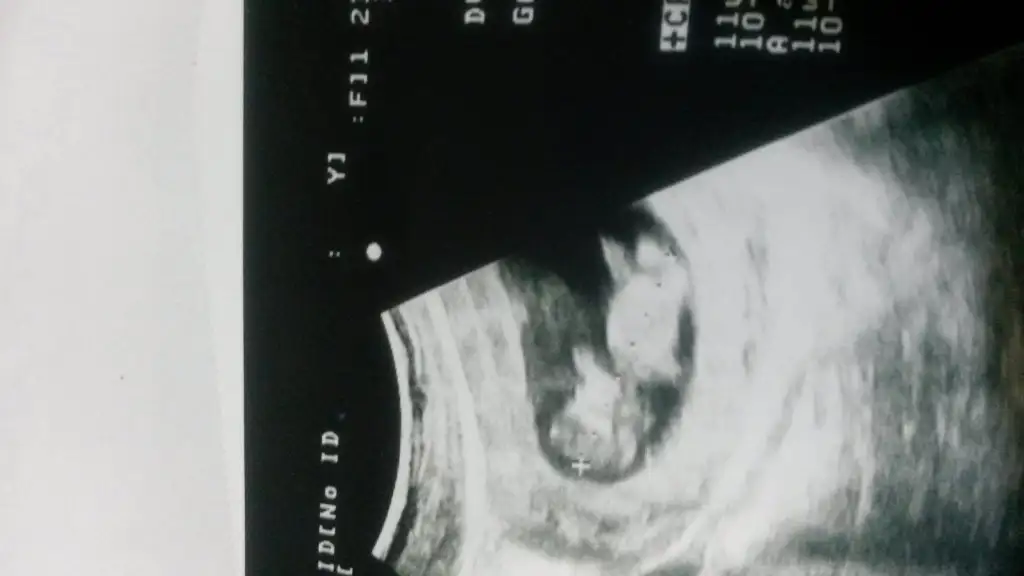

Arkadaslar 7 haftalık usg resmim bebis 8 mm oldugu icin daha net

Eklentiler

• image.webp

image.webp

40,8 KB · Görüntüleme: 643

benımkı cok net solda..ıcıme de hep erkek doguyo.bulantım da hıc olmadı.suan 9 + 5 iz.bakalım ne cıkcak..sızce ne olur merak ıcındeyım..